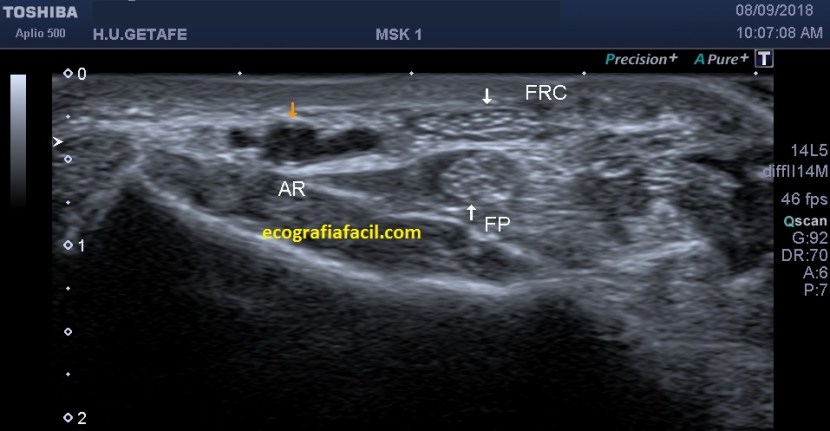

En las siguiente imágenes vemos normalidad de fibras y grosores, con grosores y alteración del patrón normal del tendón…

La imagen superior muestra un corte longitudinal del tendón tendinopático con técnica panorámica desde la inserción hasta el tercio medial de la pierna por la parte posterior, lógicamente.